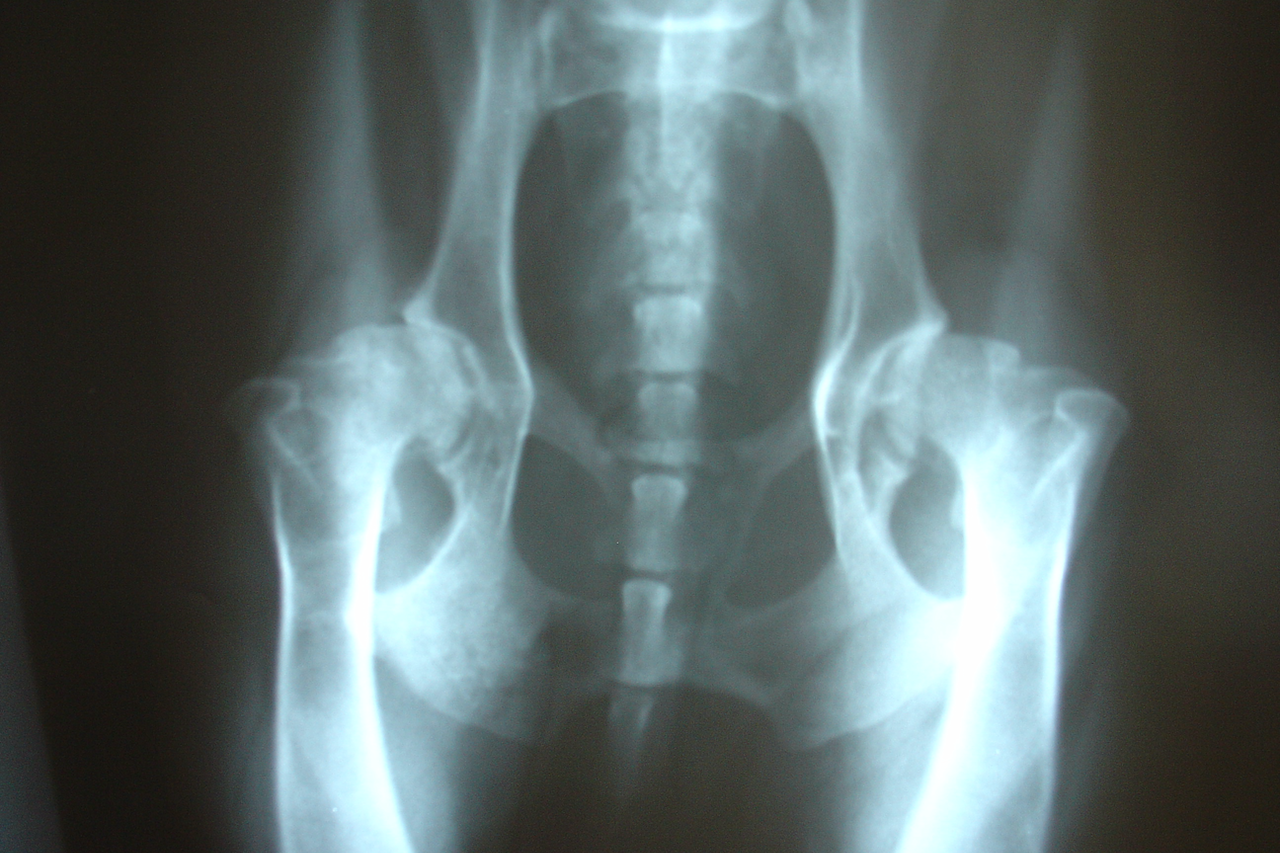

X-rays are often used to spot arthritis in dogs. They show:

🐾 Changes in bone shape and density

🐾 Signs of inflammation and fluid in the joints